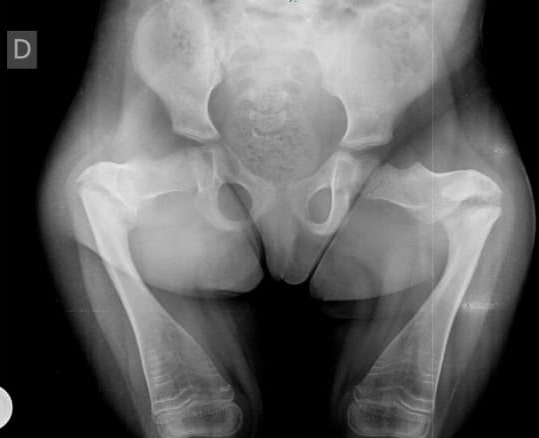

“Es una patología de origen genético, es decir, es una enfermedad adquirida desde el nacimiento. Consiste en una alteración a nivel de los huesos en los cuales los chicos sufren fracturas a repetición con traumas mínimos, a veces es una caída simple. Tiene que ver con una falla en la clasificación ósea”, manifestó el profesional.

El especialista aclaró que existen diferentes grados. “En un grado bajo, son chicos en apariencia normales, sin embargo, en la expresión más severa de la patología son chicos con baja talla, pequeños con una alteración en el crecimiento y repetidas fracturas”.

La primera paciente fue una pequeña de 5 años de edad que poseía una osteogénesis imperfecta de grado 3, una enfermedad invalidante que no le permitía caminar.